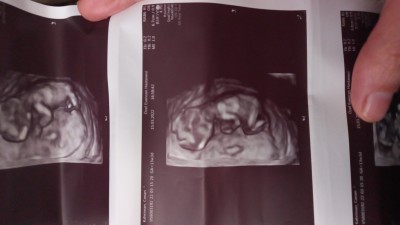

14+0 hamileyim öğrenemedim

Sizce cinsiyet ne kızlar tahminen

Kiz diyesim var ama fındık göstermemiş galiba

Kız gibi geldi bana bende yeni öğrendim aynı benim kız gibi ultrason resmi